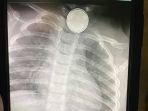

Bayinya Meninggal karena Telan Baterai, Ibu Ini Viralkan Kisahnya: Kita Butuh Produk yang Aman

Seorang bayi berusia 17 bulan meninggal dunia setelah menelan baterai remot.